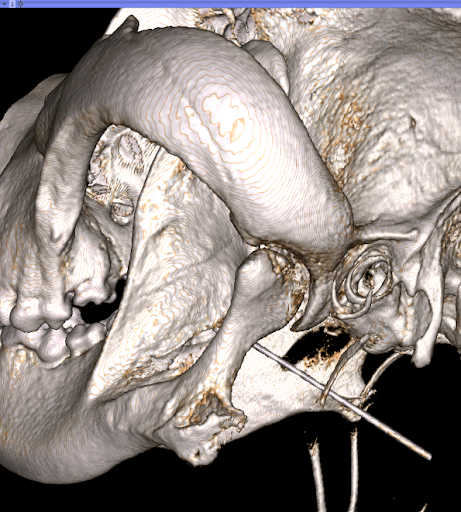

Figure 2 A TMJ in an adult dog with signs of osteoarthritis

Osteoarthritis

Osteoarthritis may occur secondary to TMJ dysplasia or as a primary cause. Osteoarthritis is the most common TMJ disorder seen in dogs. It may manifest due to age or have an underlying congenital cause. Avoiding hard chewing objects such as bones, large rawhides, antlers, and cow hooves will decrease the force on the TMJ joint. Thus, it may minimize the incidence of TMJ arthritis (as well as the incidence of fractured teeth!).

TMJ disease is diagnosed most accurately through imaging. Skull radiographs are beneficial but often are challenging to interpret as they are two-dimensional images. Cone-beam CT imaging provides 3-D evaluation and is invaluable for diagnosing TMJ disorders. This imaging modality is completed under general anesthesia, with imaging results in less than 4 minutes in most patients.